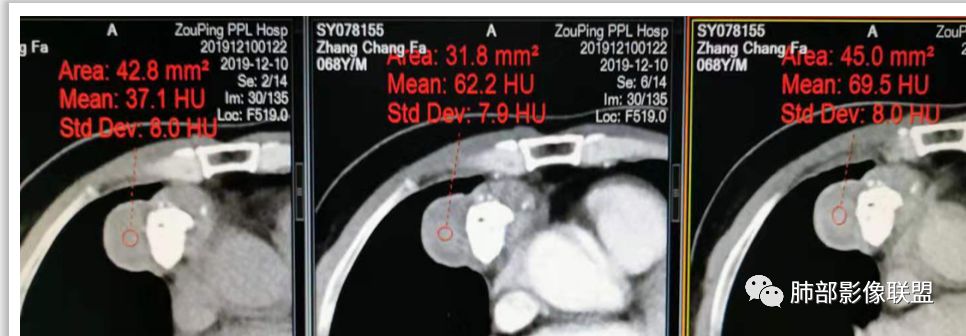

实性部分密度与肌肉类似,钙化粗大、结节状

实性部分中度强化——增加20~27HU